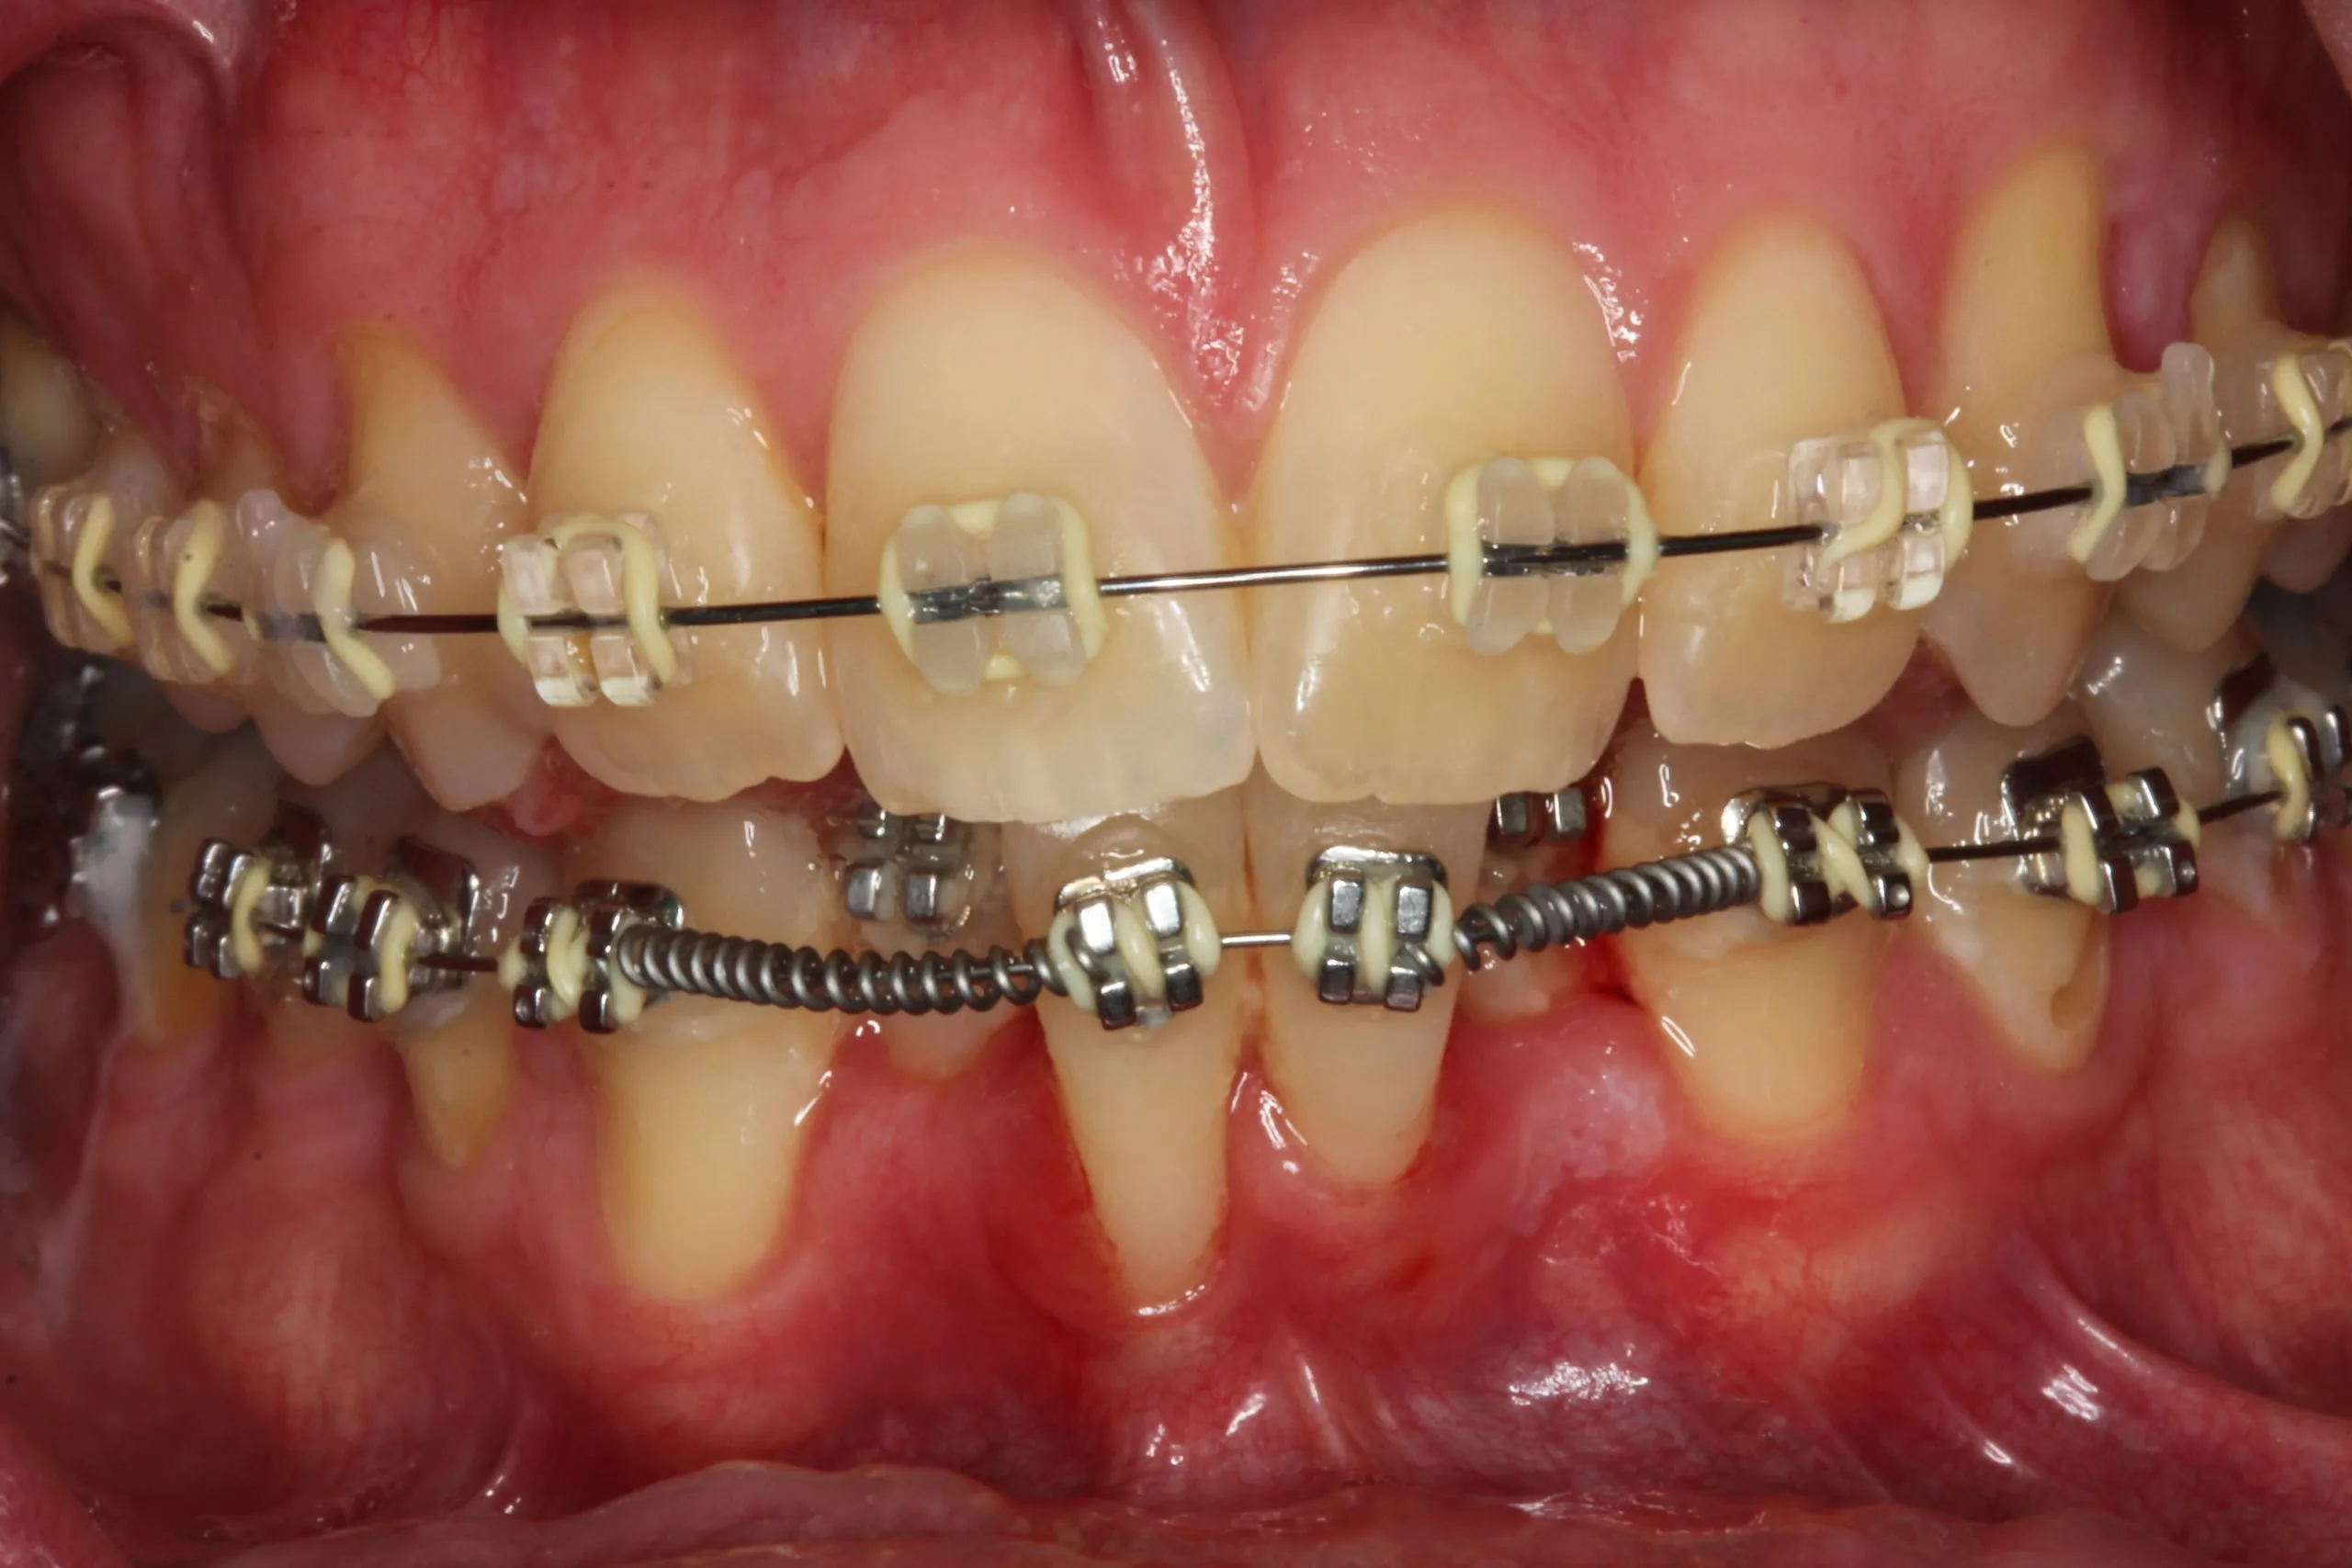

Mắc bệnh lý viêm lợi và cao răng dưới lợi diện rộng

Khách hàng bị viêm lợi, cao răng dưới lợi cũng thuộc nhóm những người không nên niềng răng. Số lượng này chiếm tới 17% trong số các ca cần trì hoãn chỉnh nha.

Cao răng, đặc biệt là cao răng dưới lợi, là nơi trú ngụ của hàng tỷ vi khuẩn gây hại. Khi gắn mắc cài, việc vệ sinh răng miệng trở nên khó khăn, tạo điều kiện cho vi khuẩn tấn công mạnh mẽ vào mô nướu đang nhạy cảm do lực siết răng. Nếu không xử lý dứt điểm, tình trạng viêm sẽ tiến triển thành túi mủ, gây đau đớn và cản trở hoàn toàn tiến độ dịch chuyển răng.

Khách hàng bị viêm lợi rất nặng do không đảm bảo vệ sinh răng miệng

Nếu gặp các tình trạng này, bác sĩ tại Lạc Việt Intech sẽ lấy sạch cao răng và điều trị miễn hó cho khách hàng. Nếu viêm lợi nhẹ, cao răng ít, việc điều trị sẽ đơn giản và nhanh chóng. Nếu nhiều cao răng dưới lợi, viêm nặng thì khách hàng có thể mất vài lần hẹn cùng bác sĩ.